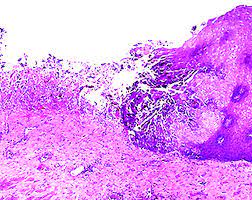

#2 most common cause of infectious esophagitis after candida self limited in healthy patients; Abstract herpes simplex virus (hsv) is a common cause of infectious esophagitis. Esophagitis caused by herpes simplex virus (hsv) is frequently documented during periods of immunosuppression in patients infected with human immunodeficiency virus (hiv). Ultimate gut formula that heals your esophagus naturally with 4 powerful nutrients. It can occur in immunocompromised patients as well as healthy individuals over a wide age range, including children and young adults. Know the real cause of esophagitis & how to heal your digestive system naturally. The key feature is acantholysis with solitary keratinocytes within the blister cavity (figures 1,2,3). The ulcer base at the left shows loss of overlying squamous epithelium with only necrotic debris remaining. Human papillomavirus is detectable in barrett's esophagus and esophageal carcinoma but is unlikely to be of any etiologic significance.. J clin virol 50 (3): Following these findings, the patient received intravenous acyclovir. Herpes simplex virus multiple superficial ulcers are common (details from endoscopy) biopsy edge of ulcer — intranuclear inclusions found in squamous mucosa can see detached squamous cells as well as macrophages with viral incusions in ulcer slough inclusions are usually obvious Can perform cmv immunostain if no classic viral cytopathic effect seen on h&e.

The diagnosis of herpes simplex virus (hsv) esophagitis is made at endoscopy. Recommended in any case of esophageal ulceration as the diagnostic features can be easily obscured by the intense background inflammation. Herpes simplex virus multiple superficial ulcers are common (details from endoscopy) biopsy edge of ulcer — intranuclear inclusions found in squamous mucosa can see detached squamous cells as well as macrophages with viral incusions in ulcer slough inclusions are usually obvious The low power pattern of a typical lesion is of an intraepidermal blister (figure 1). May cause esophageal perforation or disseminate in immunocompromised patients may have secondary bacterial or fungal infections must rule out hsv infection as cause of esophageal ulcers, particularly from immunocompromised patients It's caused by the herpes simplex virus. The aim of this retrospective study is to identify comorbid and predisposing conditions and sequelae of hsv esophagitis in immunocompetent children. It can be a consequence of viraemia, reactivation of hsv, or even a direct spread of the virus to oesophageal mucosa from the vagus nerve in immunocompromised patients.